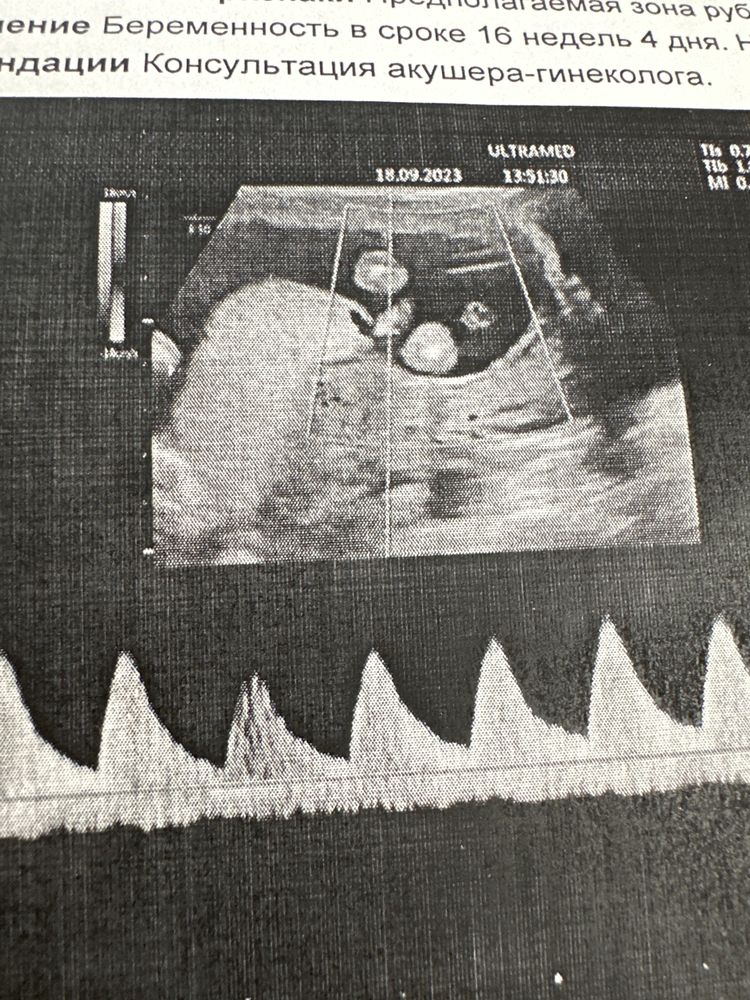

Девочки, привет! Я уже всех умучила и себя тоже. 16 недель. На фото вид снизу, ребенок поджимает ножки, визуализация затруднена. Врач с самого начала предположила девочку, но потом сказала, что не уверенна и предложила пол посмотреть позже на втором скрининге. Вы кого видите?

Belko, это ножки поджатые. По середине отросток. Вопрос кому он принадлежит мальчику или девочке? А кровь, да) пожалуй сдам!

Если попа слева, то я бы предположила девочку. Но ракурс не очень удачный.